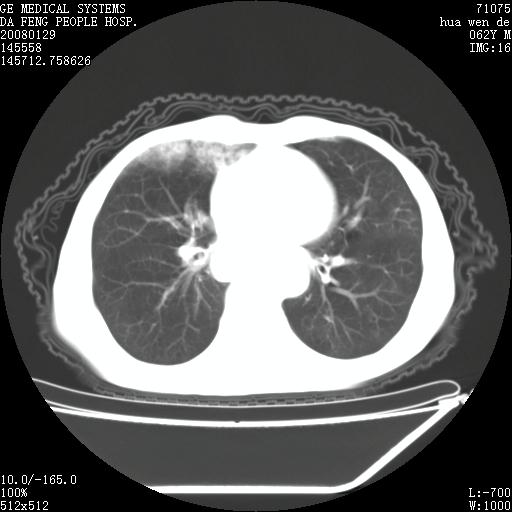

1.整个食管扩张,未见明显占位性病变,贲门区亦未见明显占位病变,考虑:贲门失驰缓症;

2.右上肺病变边缘可见毛刺,囊壁厚度不均匀,周围境界较清楚,未见炎性渗出性影,右上肺外带可见片状影,边缘不清,考虑:肺癌伴空洞形成、右上肺炎。

15楼主分析有道理,胸腔胃除外,那么考虑贲门失驰缓症并肺部化脓感染(吸入性)可能。

肺内病灶位于右肺中叶,食道扩张后导致咽部功能受影响,吸入气管可能是存在的。

可疑之处在于:左肺未见吸入性病灶存在。另右肺癌(右肺中央型并阻塞性肺炎)不能除外

食管全程扩张,壁均匀不厚,喷门失弛缓症

右上肺空洞可见液平,临近肺野磨玻璃密度,考虑1.结核2.脓肿